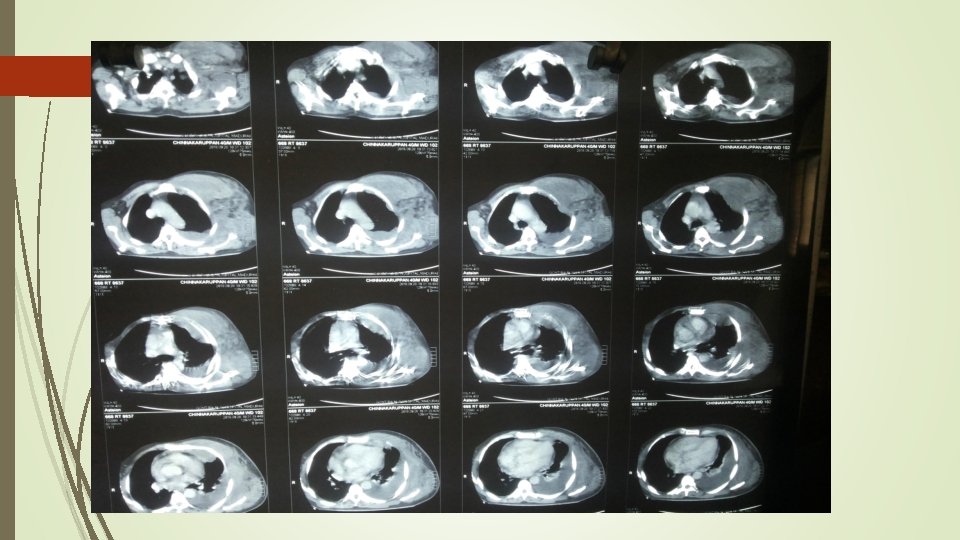

CT CHEST – PLAIN - left side minimal pleural effusion with soft tissue edema CT CHEST - CONTRAST - inflammatory muscular enlargement with associated edema noted on anterior and lateral chest wall of left side, associated with fat stranding and fascial thickening. No evidence of abscess formation